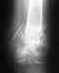

Перелом обоих бедер получен в результате ДТП. 03.05.07.DS: поперечные переломы обоих бедер в средней трети. Травматический шок II. Травматическая болезнь осложнилась жировой эмболией, дистресс синдромом.

Перелом обоих бедер получен в результате ДТП. 03.05.07.DS: поперечные переломы обоих бедер в средней трети. Травматический шок II. Травматическая болезнь осложнилась жировой эмболией, дистресс синдромом. 04.05.07 ос левого бедра ретроградным блокируемым стержнем;ос правого бедра ретроградным блокируемым стержнем.07.05.07 н/трахеотомия.03.05.07 - 21.05.07 находился в отделении РАО.Получал анальгетики, десенсибилизирующие, противоотечные, антибиотикотерапию, инфузионную терапию, энтеральное питание, сосудистую терапию. Перелита Er масса, без осложнений. Заживление per-I, швы сняты. ОАК, ОАМ, БХ в пределах нормы На контрольных рентгенограммах положение отломков удовлетворительное. В удовлетворительном состоянии выписан 08.06.07.Через 5 месяцев после травмы были удалены блокирующие статические винты под местным обезболиванием.Вопрос: через какой период времени можно удалять стержни? Предлагают удалить стержни через 7,5 месяцев. Операцию по удалению стержней будут проводить под общим наркозом. Нет ли противопоказаний к общиму наркозу после жировой эмболии?